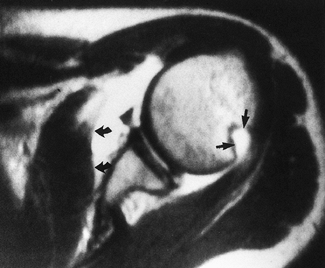

Similarly, large Hill–Sachs or reverse Hill–Sachs lesions,

posterolateral or anterolateral humeral head impaction fractures

respectively, can affect this articular relationship (Fig. 80.2) (22,131,133,134).

These fractures are created by direct contact between the humeral head

and the glenoid rim during shoulder dislocations. While these lesions

are present in more than 80% of anterior dislocations and 25% of

anterior subluxations, they are rarely a contributing factor to

instability. They become biomechanically relevant to joint stability

when osteoarticular loss involves greater than 30% of the humeral head

surface.

![]() |

|

Figure 80.2. Axial MRI with contrast demonstrates anterior capsular stripping (large curved arrows) with an associated Bankart lesion. In addition, a large Hill–Sachs lesion can be seen posteriorly (smaller straight arrows).